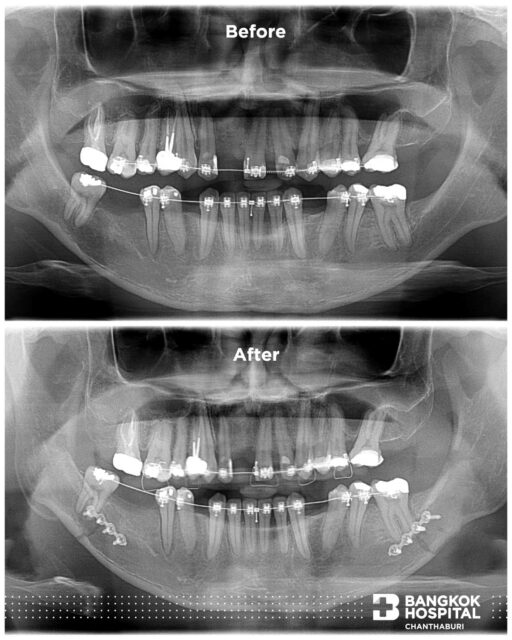

ยิ้มอย่างมั่นใจ ให้เราดูแลสุขภาพฟันและช่องปาก